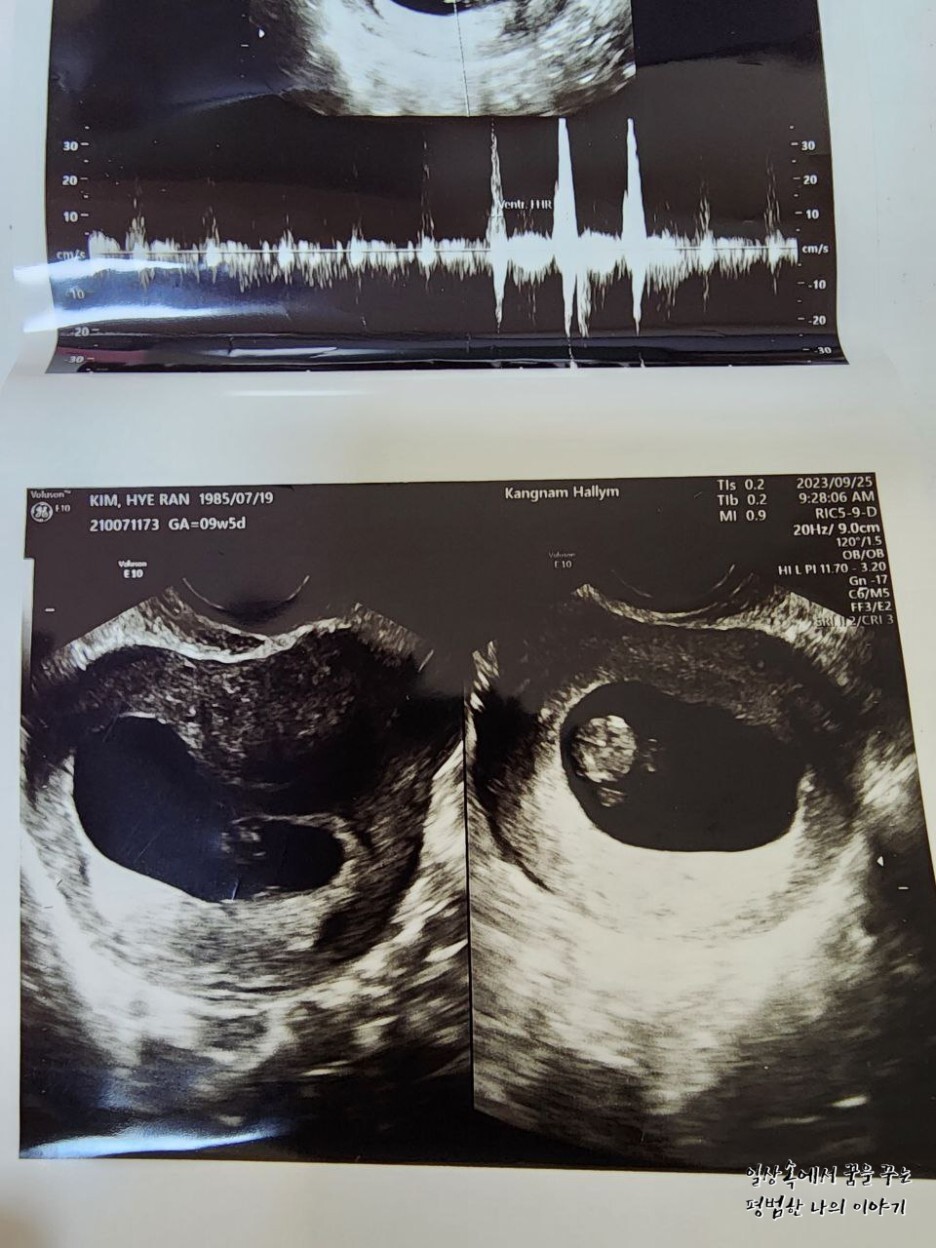

EDD(Expected Date of Delivery, 출산 예정일): 2024년 4월 21일

CRL(Crown-Rump Length, 태아의 머리부터 엉덩이까지의 길이): 31.71mm

2주 만에 만난 레오나는 여전히 내 눈에 귀여운 젤리 곰 형태를 하고 있었다. 2주 사이에 16.72mm에서 31.71mm로 두 배나 길어져 있었다. 31.71mm라고 해봐야 정말 콩알만 한 크기이지만 그 작은 크기에도 얼굴, 손 그리고 발까지 초음파로 확인이 가능하다. 출산 예정일은 지난번에 비해 3일 앞당겨졌는데 아기의 크기에 따라 계속 바뀔 수 있으므로 대략 4월 셋째 주쯤 출산하겠구나 예상하고 계획을 짜기 시작했다.